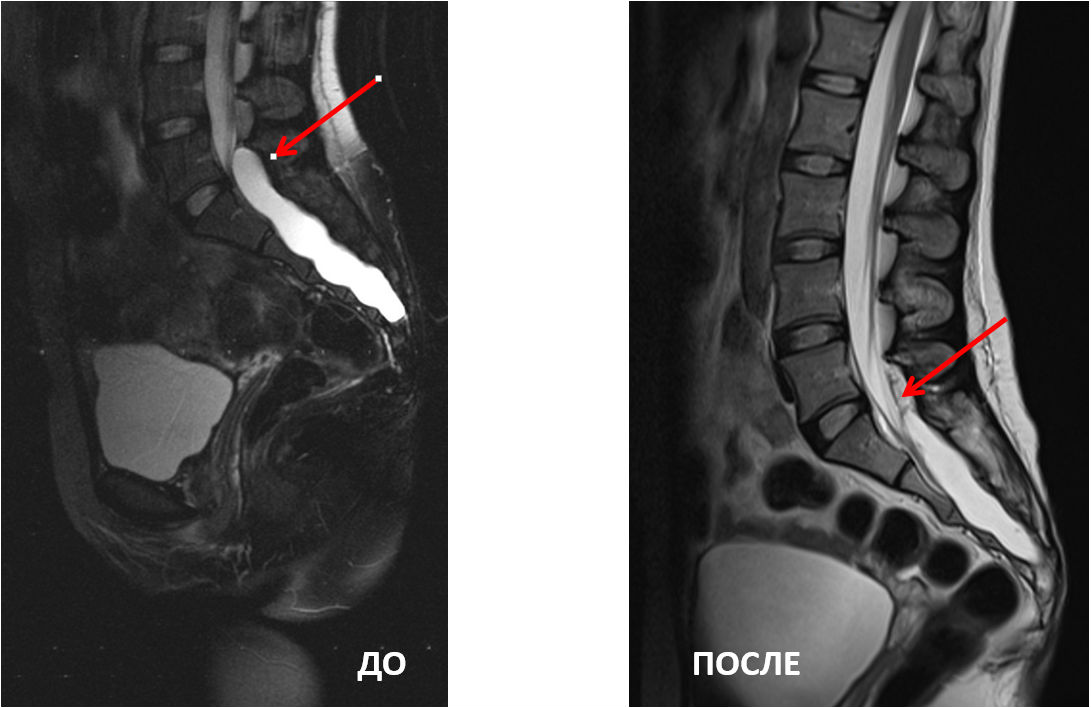

МРТ-снимки до и после удаления тарловых кист

«У нашей пациентки тарловы кисты поражали весь крестцовый канал: от поясницы до копчика с выходом на переднюю поверхность крестца. Одна из кист сдавливала S1 корешок справа, что и вызывало выраженный болевой синдром», — объясняет нейрохирург

«Было принято решение проводить вмешательство через небольшой прокол на уровне L5S1. С помощью эндоскопического оборудования убрали часть кисты, освободив пространство корешка S1. Оперативное лечение увенчалось успехом, боль у пациентки прошла. Уже на третий день она была выписана из клиники», — рассказывает нейрохирург.